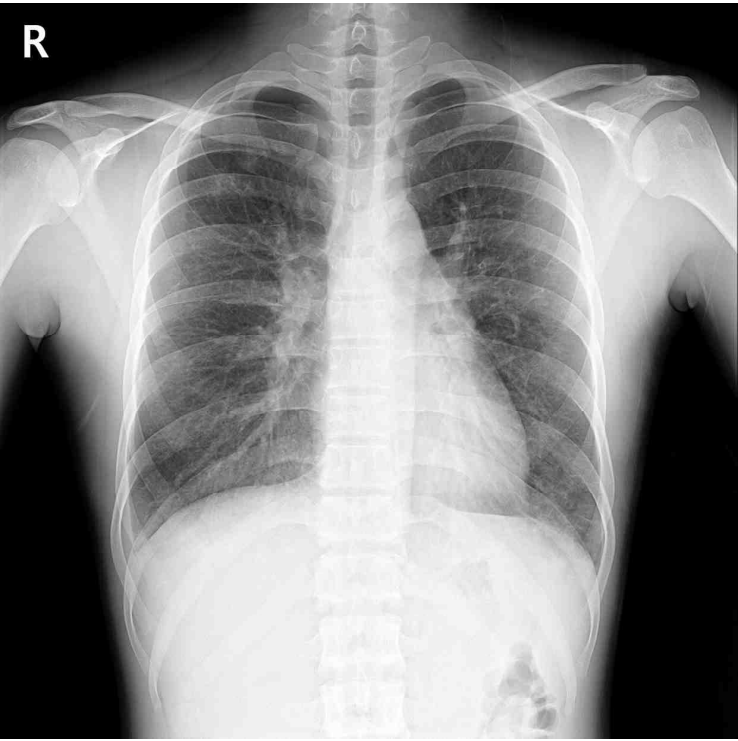

62세 남자가 4개월 전부터 기침과 가래가 있다며 병원에 왔다. 높은 언덕을 올라갈 때 숨이 찬다. 35갑•년의 흡연력이 있으며, 3년 전부터 금연하고 있다. 심음과 호흡음은 정상이다. 가슴 X선 사진이다. 기관지 확장제 투여 전후 폐기능검사 결과는 다음과 같다. 치료는?

CXR: Lung hyperinflation

• 신체 진찰에서 심음과 호흡음은 정상으로 확인되었다. 그러나 35갑년의 흡연력이 있는 점, 흉부 X선 검사에서 lung hyperinflation 소견이 확인되는 것을 감안하면 만성폐쇄성폐질환을 증상의 원인으로 고려할 필요가 있다.

CXR: Hyperinflated lungs, barrel chest